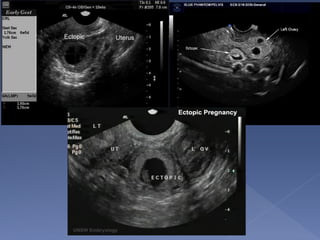

 Direct visualization

of ectopic

pregnancy

 Only seen in 10-20%

pregnancies

 Empty uterus

 Pseudo gestational

sac

 Sac is intra-decidual

 No yolk sac or fetal

pole at sac

diameter of 25 mm

or more

transvaginally

 Sac can be irregular

 Low uterine position

 Weak decidual

reaction

 If unsure repeat in 1

week